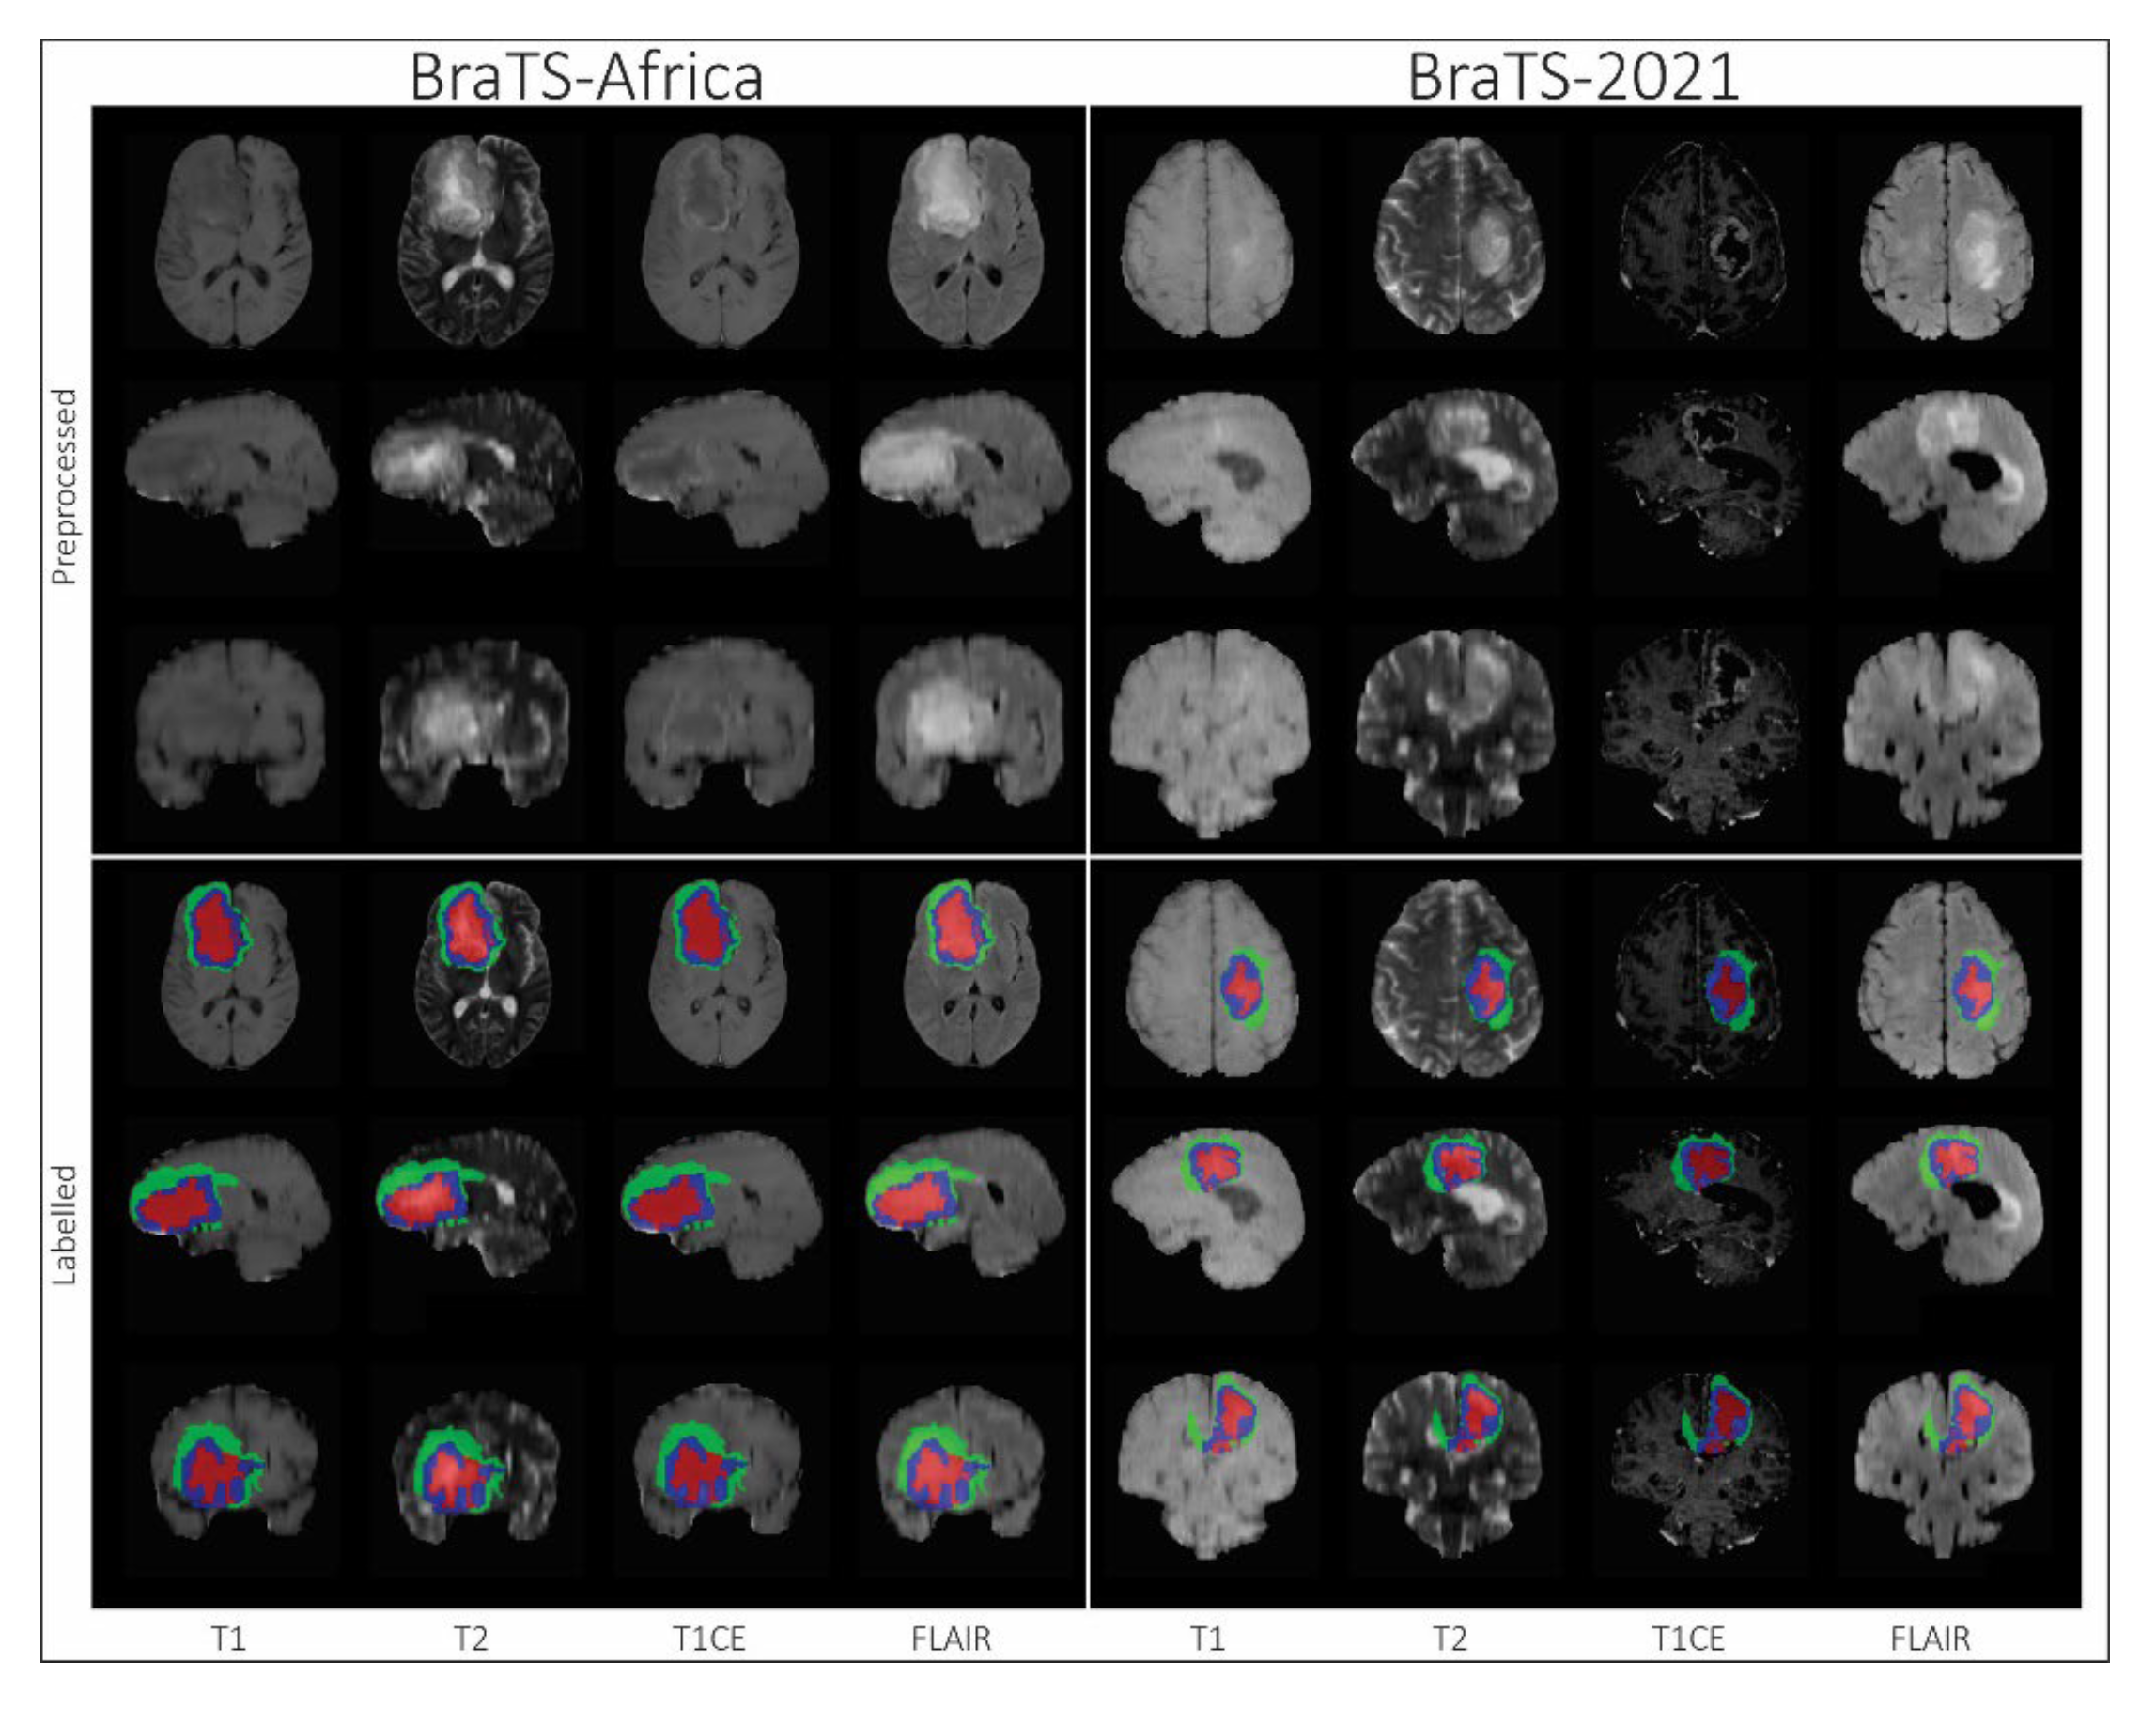

Segmentation - BraTS-Africa: BraTS Challenge on Sub-Sahara-Africa Adult Glioma: The BraTS-Africa Challenge focuses on addressing the disparity in glioma treatment outcomes between high-income regions and Sub-Saharan Africa (SSA), where survival rates have not improved significantly due to factors such as the use of lower-quality MRI technology (see Figure ii), late-stage disease presentation, and unique glioma characteristics. This initiative is part of a broader effort to adapt and evaluate computer-aided diagnostic (CAD) tools for glioma detection in resource-limited settings, where they have the potential to make a significant impact on healthcare.The MICCAI-CAMERA-Lacuna Fund BraTS-Africa 2023 Challenge has assembled the largest publicly available retrospective cohort of pre-operative glioma MRI scans from adult Africans, including both low-grade glioma (LGG) and glioblastoma/high-grade glioma (GBM/HGG). These scans, obtained as part of routine clinical care from multiple institutions, encompass all four MRI modalities: T1, T1Gd, T2, T2-FLAIR. The BraTS-Africa challenge involves developing machine learning algorithms to automatically segment intracranial gliomas into three distinct classes using a new 3-label system. The sub-regions for evaluation are "enhancing tumor" (ET), "non-enhancing tumor core" (NETC), and "surrounding non-enhancing FLAIR hyperintensity" (SNFH), which are crucial for enhancing diagnostic accuracy and treatment planning in these underserved populations [10,25];

- Segmentation - Adult Glioma: RSNA-ASNR-MICCAI BraTS Continuous Evaluation Challenge : Same Pre-processing data protocol as BraTS 2021;

- Segmentation - BraTS-Africa: BraTS Challenge on Sub-Sahara-Africa Adult Glioma: The pre-processing pipeline used for the BraTS-Africa 2023 challenge data was identical to that applied in the BraTS 2017-2022 challenges [25]. This pre-processing pipeline is publicly available through the Cancer Imaging Phenomics Toolkit (CaPTk) and the Federated Tumor Segmentation (FeTS) tool;

Segmentation - BraTS-Africa Dataset: All imaging data were reviewed and manually annotated by board-certified radiologists specializing in neuro-oncology, following the BraTS pre-processing and annotation protocols [10]. The new BraTS segmentation labeling introduced in 2023, and also used for the BraTS-Africa 2023 challenge, considers the following tumor sub-regions and can be visualised in Figure ii: